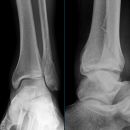

Sprunggelenk

Weber A

Es wurden keine Bilder gefunden.

Weber B

Weber C + dorsales Volkmann

Trimalleoläre

Vorderes Volkmann + lat. Talusschulter